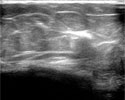

Все этапы лечения производятся под непрерывным ультразвуковым контролем.

"До" и "после" лечения.